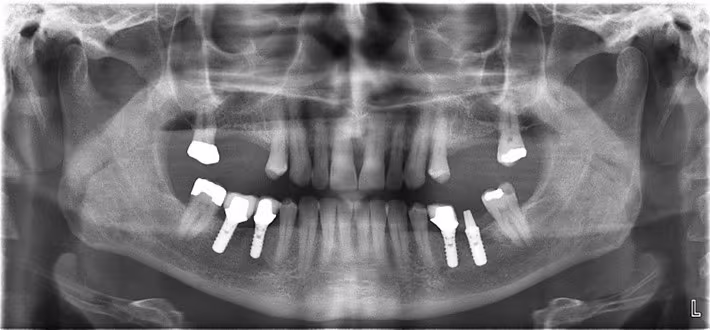

Figure 21. Optimal Panoramic Image.

In reality, most panoramic images are not optimal nor ideal but rather present with minor yet acceptable error(s) that do not interfere with diagnosis and treatment planning. In such instances, a retake is not justified.